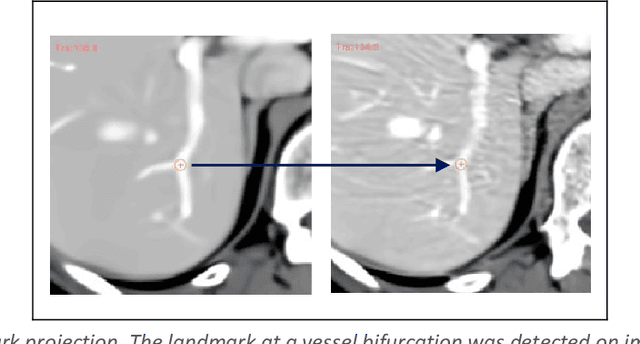

Abstract:Purpose: Evaluating deformable image registration (DIR) algorithms is vital for enhancing algorithm performance and gaining clinical acceptance. However, there's a notable lack of dependable DIR benchmark datasets for assessing DIR performance except for lung images. To address this gap, we aim to introduce our comprehensive liver computed tomography (CT) DIR landmark dataset library. Acquisition and Validation Methods: Thirty CT liver image pairs were acquired from several publicly available image archives as well as authors' institutions under institutional review board approval. The images were processed with a semi-automatic procedure to generate landmark pairs: 1) for each case, liver vessels were automatically segmented on one image; 2) landmarks were automatically detected at vessel bifurcations; 3) corresponding landmarks in the second image were placed using the deformable image registration method; 4) manual validation was applied to reject outliers and confirm the landmarks' positional accuracy. This workflow resulted in an average of ~68 landmark pairs per image pair, in a total of 2028 landmarks for all 30 cases. The general landmarking accuracy of this procedure was evaluated using digital phantoms. Estimates of the mean and standard deviation of landmark pair target registration errors (TRE) on digital phantoms were 0.64 and 0.40 mm. 99% of landmark pairs had TREs below 2 mm. Data Format and Usage Notes: All data are publicly available at Zenodo. Instructions for using our data and MATLAB code can be found on our GitHub page. Potential Applications: The landmark dataset generated in this work is the first collection of large-scale liver CT DIR landmarks prepared on real patient images. This dataset can provide researchers with a dense set of ground truth benchmarks for the quantitative evaluation of DIR algorithms within the liver.